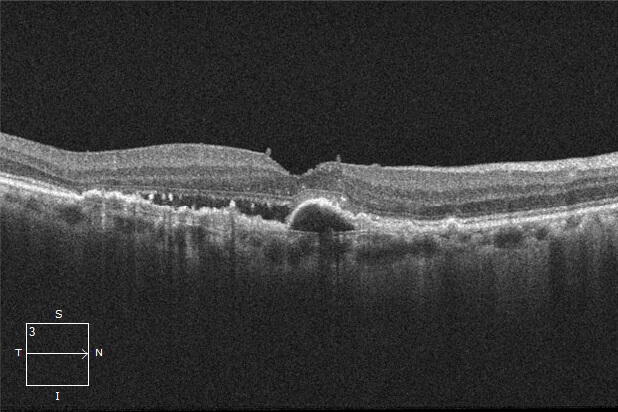

加齢黄斑変性のOCT

黄斑の下には網膜色素上皮があり、さらにその下に脈絡膜があります。血管の詰まりなどにより網膜の栄養や酸素が不足すると、それを補うために脈絡膜新生血管が作られます。この脈絡膜新生血管はもろくて破れやすく、血液の成分が漏れることがあります。

滲出型では脈絡膜新生血管が発生し、網膜の腫れや出血などを起こすタイプです。